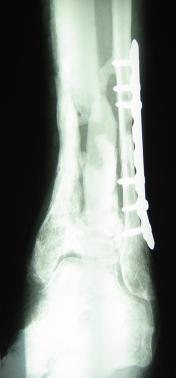

Post-corrective surgery X-Rays of the damaged right & left legs / ankles

The first two x-rays show Liam’s left ankle and pelvis prior to the accident. For comparison purposes it is interesting to see the

differences. The next x-rays were taken after the corrective surgery performed by Dr. Armendariz. Noticed that Dr. Armendariz has used tibia

bracing and also aligned the bone fragments of the left leg so that they could heal in the proper orientation. The external fixation has been

removed and Liam’s left foot has been returned to a more natural alignment.